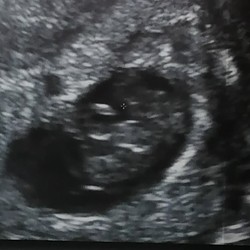

ik ben namelijk 10 dagen en 1 dag zwanger.

En het echo kunnen we nog steeds niks zien

Mijn instellingen zijn te laag

Voor tips. Want ik ben 10 weken zwanger

Dus hormonen zijn te laag?????

Veel bloed laten prikken. En elke keer zie ik geen baby 😩